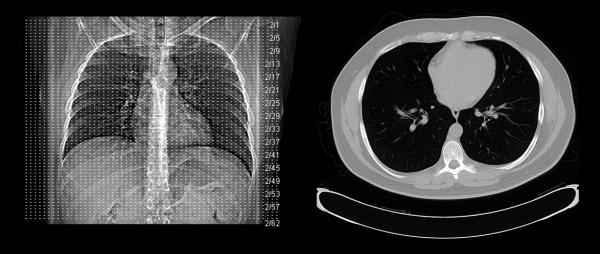

Americans are regularly exposed to low levels of radiation during CT scans, fueling media speculation that this routine medical procedure is driving an epidemic of cancers. Is there any truth to the CT scan-cancer association? Let's look at the data.

Are CT scans silently triggering a cancer epidemic — or are we being misled by speculative modeling and media-fueled fear? A new article warns of 103,000 additional cancers from diagnostic imaging, yet offers no empirical evidence, just an alarming prediction based on a controversial theory. Before we let panic dictate policy, it’s worth asking: where’s the data?